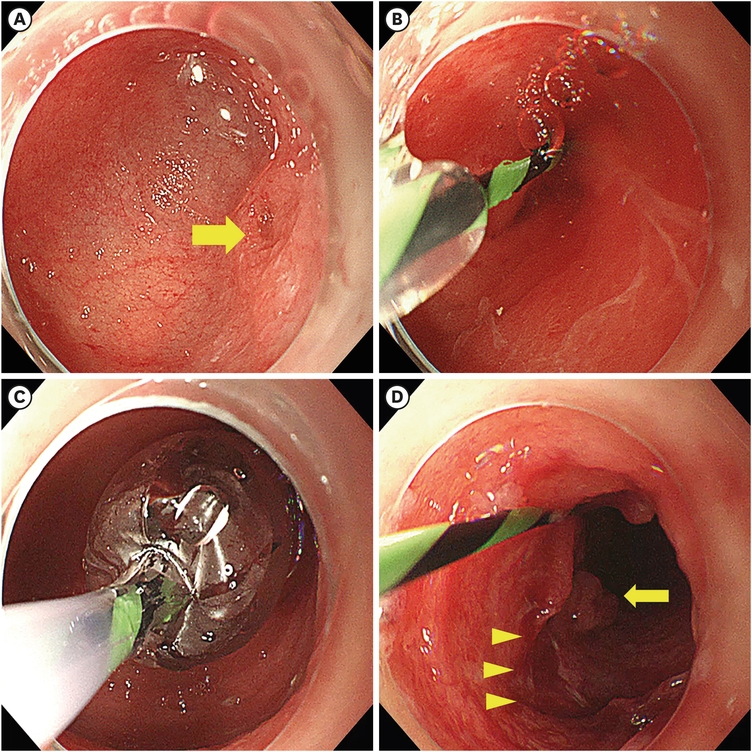

The patient was referred to the Department of Pediatric Surgery. After consultation with a pediatric gastroenterologist, endoscopic intervention was attempted as the initial approach. The pediatric surgeon was on standby for emergent complications. Endoscopy was performed with the patient under general anesthesia using a flexible endoscope. A dilated duodenum and membranous stenosis with small openings were also observed (Fig. 2A). A guidewire was carefully introduced into the opening (Fig. 2B), followed by a multi-diameter dilation balloon (CRE™ PRO wire-guided balloon dilatation catheter, Boston Scientific, Product Code M00558640). The balloon was incrementally expanded from 10 to 18 mm, with each inflation lasting 1 minute (Fig. 2C). A mucosal tear was confirmed after repeated expansions with no evidence of perforation or bleeding. The ampulla of Vater was found immediately below the web, and no additional strictures were observed in the distal intestine (Fig. 2D).

Fig. 2

Balloon dilatation of the duodenal web. (A) Endoscopy reveals a dilated duodenal bulb with a tiny lumen (arrow). (B, C) A guiding catheter is passed through the opening, and balloon dilatation is performed, increasing from 10 mm to 18 mm. The diameter of inflation did not exceed the caliber of the duodenum. (D) Stenosis markedly improves after ballooning. A post-dilatation mucosal tear (arrowhead) and the ampulla of Vater (arrow) are observed.